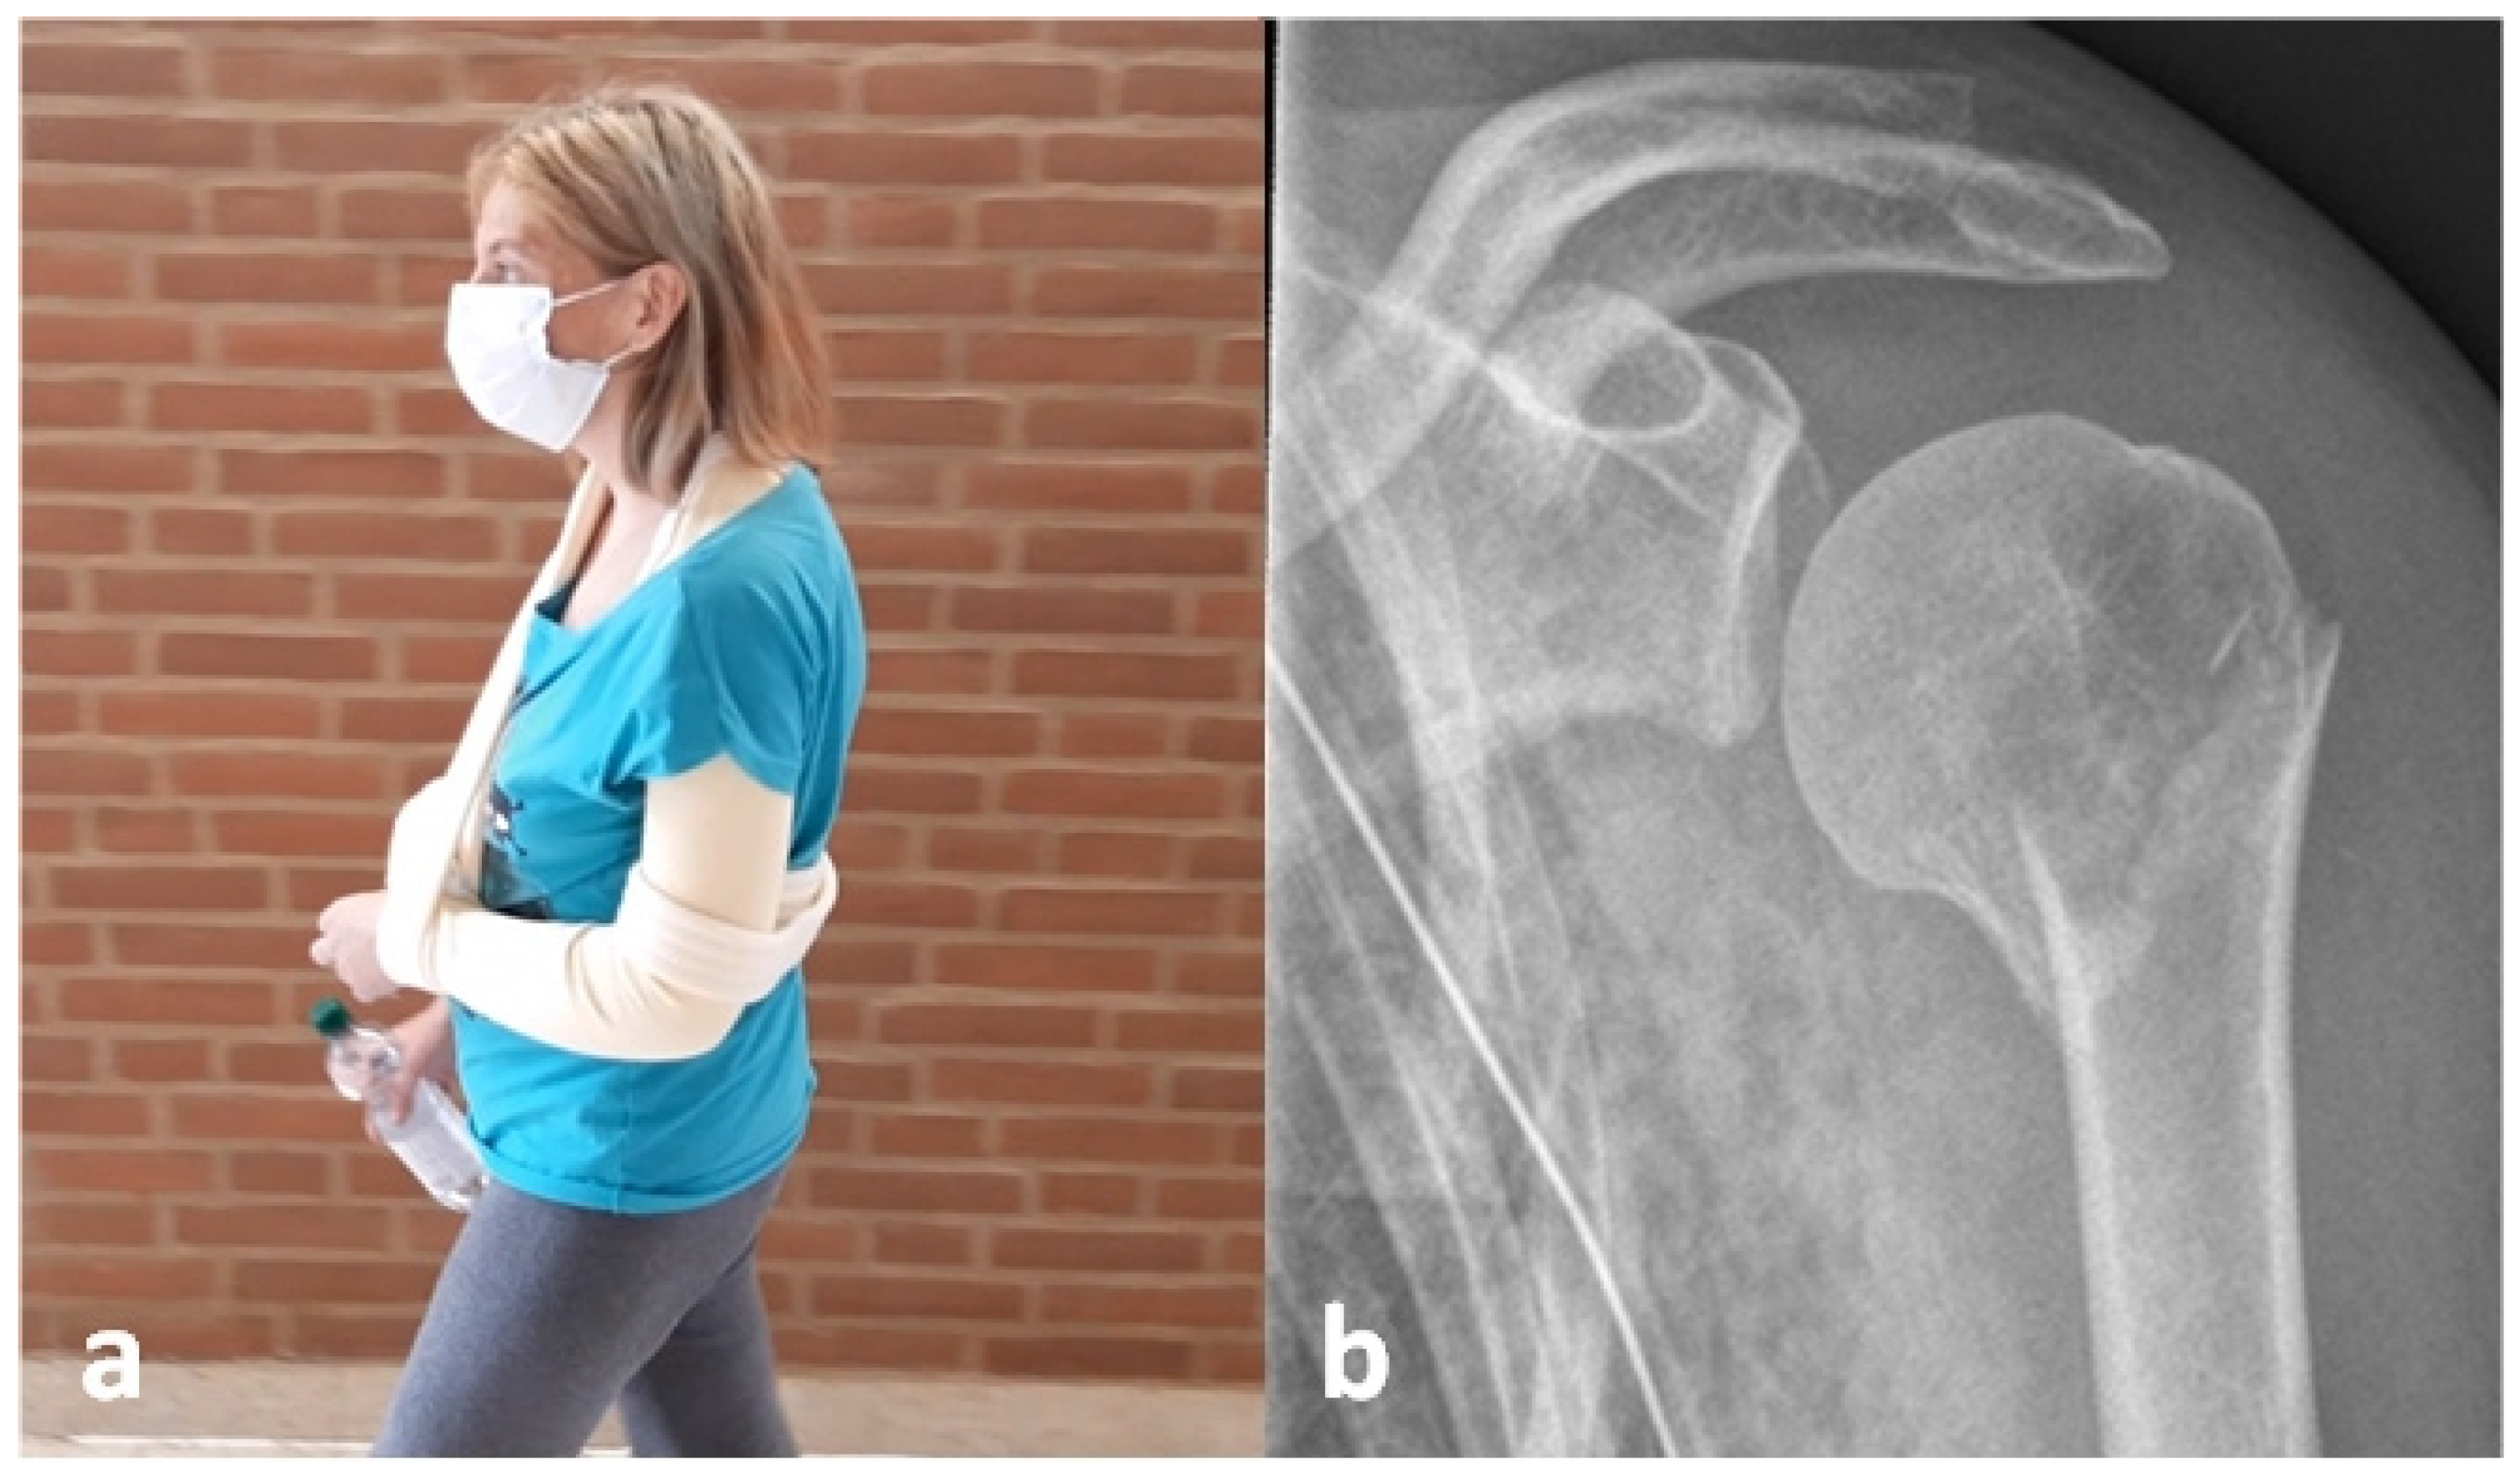

Diagnostics Free Full Text Self Reduction In Proximal Humerus